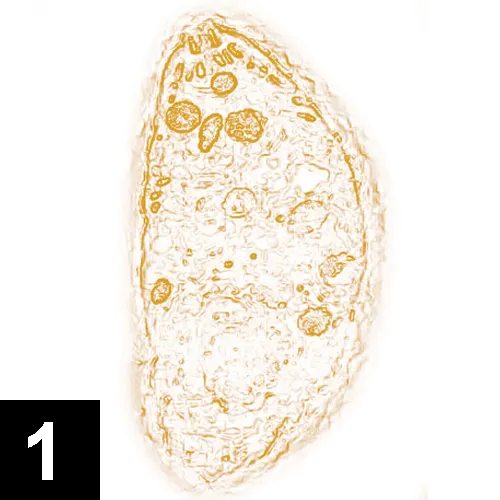

A microscopic view of a single-celled organism, displaying an elongated shape with a textured surface and various internal structures. The organism is stained in shades of orange, highlighting its cellular components against a bright background.

Image 1. Toxoplasma gondii